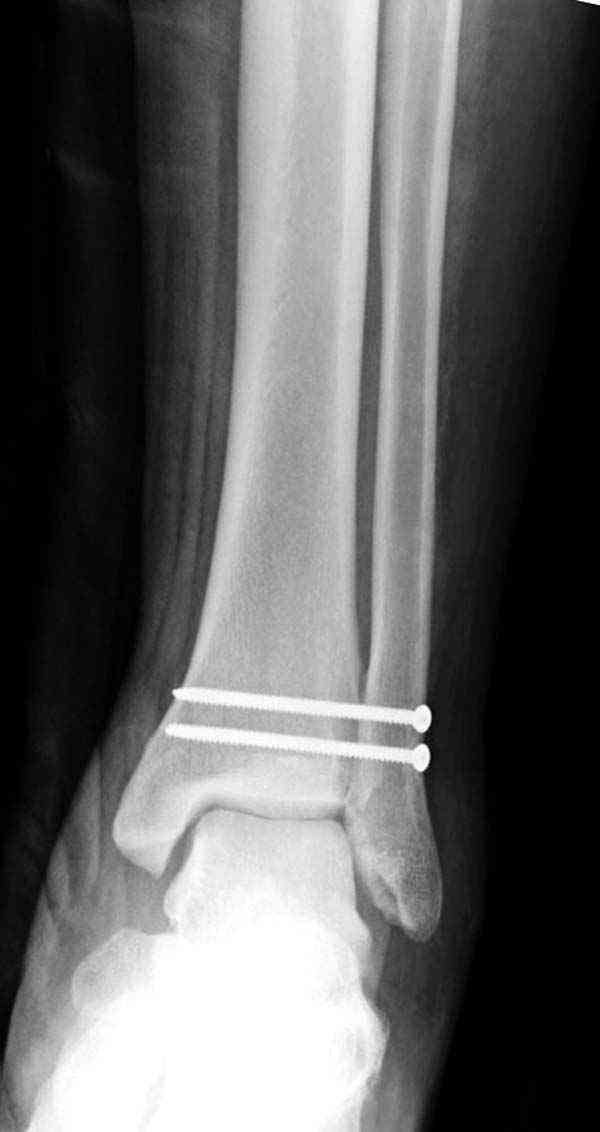

Нет первичных снимков, перелом очень низкий и под большим сомнением диагноз разрыва синдесмоза. Медиальная сторона отрепонирована на "хорошо" и, по-видимому, прорезание проволоки произошло во время операции. Без снимков трудно судить о высоте малоберцовой, а лодыжка находится в варусе. Лагирование получилось, но возле тонких шурупов передне-задний шуруп выглядит немного тяжеловато.

Медиальная лодыжка фиксируется каннюлированными лодыжечными шурупами перкутанно, а неточная репозиция (интерпозиция) является показанием к открытой технике. При больших вертикальных фрагментах нужны противоскользящие медиальные пластины.

При лечении синдесмоза количество шурупов не имеет значения. Два через три кортекса или один через все кортикальные слои механически одинаковы.